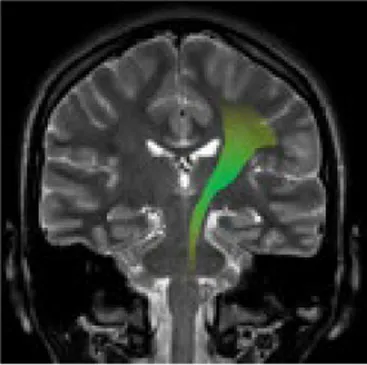

Studying the SNDG with conventional MRI, disruption to global functional connectivity has been revealed in the ipsi-lesional corticospinal tract and in the inter-hemispheric connections (corpus callosum), in the bilateral inferior fronto-occipital fasciculus and in the bilateral superior longitudinal fasciculus (34–36), in the ipsilateral thalamus, in the substantia nigra, hippocampus and in amygdala (37–39).

The involvement of these areas distal to the primary lesion defines the onset of cognitive and behavioral symptoms different from those primarily related to stroke area (36, 40). For example, involvement of the thalamus can lead to hyperalgesia; damage in the substantia nigra provokes Parkinson-like symptoms (slow movements, tremor, stiffness and difficulty with walking and balance); involvement of amygdala results in difficulty with memory processing and emotional reactions, whereas an involvement of hippocampus to memory impairment (Table 1).